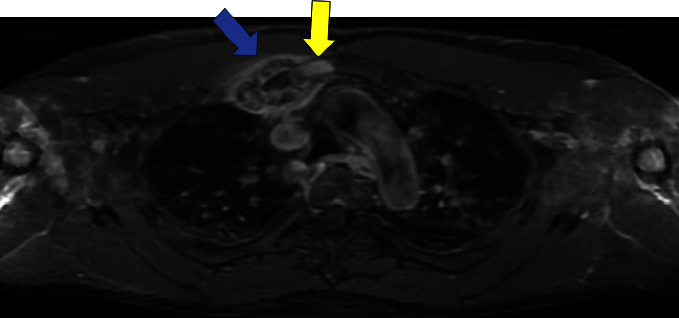

SAPHO综合征是一种罕见的骨、关节和皮肤炎症性疾病,因出现滑膜炎、痤疮、脓疱病、骨质增生和骨炎而得名。SAPHO综合征的标志包括骨关节和皮肤表现,然而,与炎症性肠病(特别是克罗恩病)的罕见关联已被记录。关于SAPHO综合征与炎症性肠病(IBD),特别是溃疡性结肠炎(UC)之间关系的文献仍然有限。我们报告一个不寻常的病例SAPHO综合征患者UC。胸部x线及MRI显示右侧第一肋骨及邻近胸骨肿大。骨显像显示肋软骨连接处骨质增生和强直,骨活检显示骨和肋软骨反应性,未见感染或恶性肿瘤。使用唑来膦酸4个月后症状完全缓解,无明显不良反应。SAPHO综合征在IBD患者中诊断罕见,在UC患者中更是如此,这可能是由于SAPHO综合征的临床异质性以及与IBD的肠外表现重叠导致的漏诊。我们的治疗方法为UC中SAPHO综合征的诊断和治疗文献提供了重要的数据。

SAPHO syndrome, a rare inflammatory disorder of bone, joints, and skin, is named based on the presence of synovitis, acne, pustulosis, hyperostosis, and osteitis. The hallmark of SAPHO syndrome includes osteoarticular and dermatologic manifestations, however, rarer associations with inflammatory bowel disease (particularly Crohn's disease) have been documented. The literature on the relationship between SAPHO syndrome and inflammatory bowel disease (IBD), especially ulcerative colitis (UC), remains limited. We report an unusual case of SAPHO syndrome in a patient with UC. Chest x-ray and MRI showed enlargement of the right first rib and adjacent sternum. Bone scintigraphy revealed hyperostosis and ankylosis of the costochondral junction, and bone biopsy revealed reactive bone and costal cartilage without findings of infection or malignancy. Complete resolution of symptoms was achieved 4 months after starting zoledronic acid without significant adverse events. The diagnosis of SAPHO syndrome in IBD patients is rare, even more so in UC patients, likely attributable to underdiagnosis given the clinical heterogeneity of SAPHO syndrome and overlap with the extra-intestinal manifestation of IBD. Our treatment approach provides critical data to the underreported literature on diagnosis and managing SAPHO syndrome in UC.